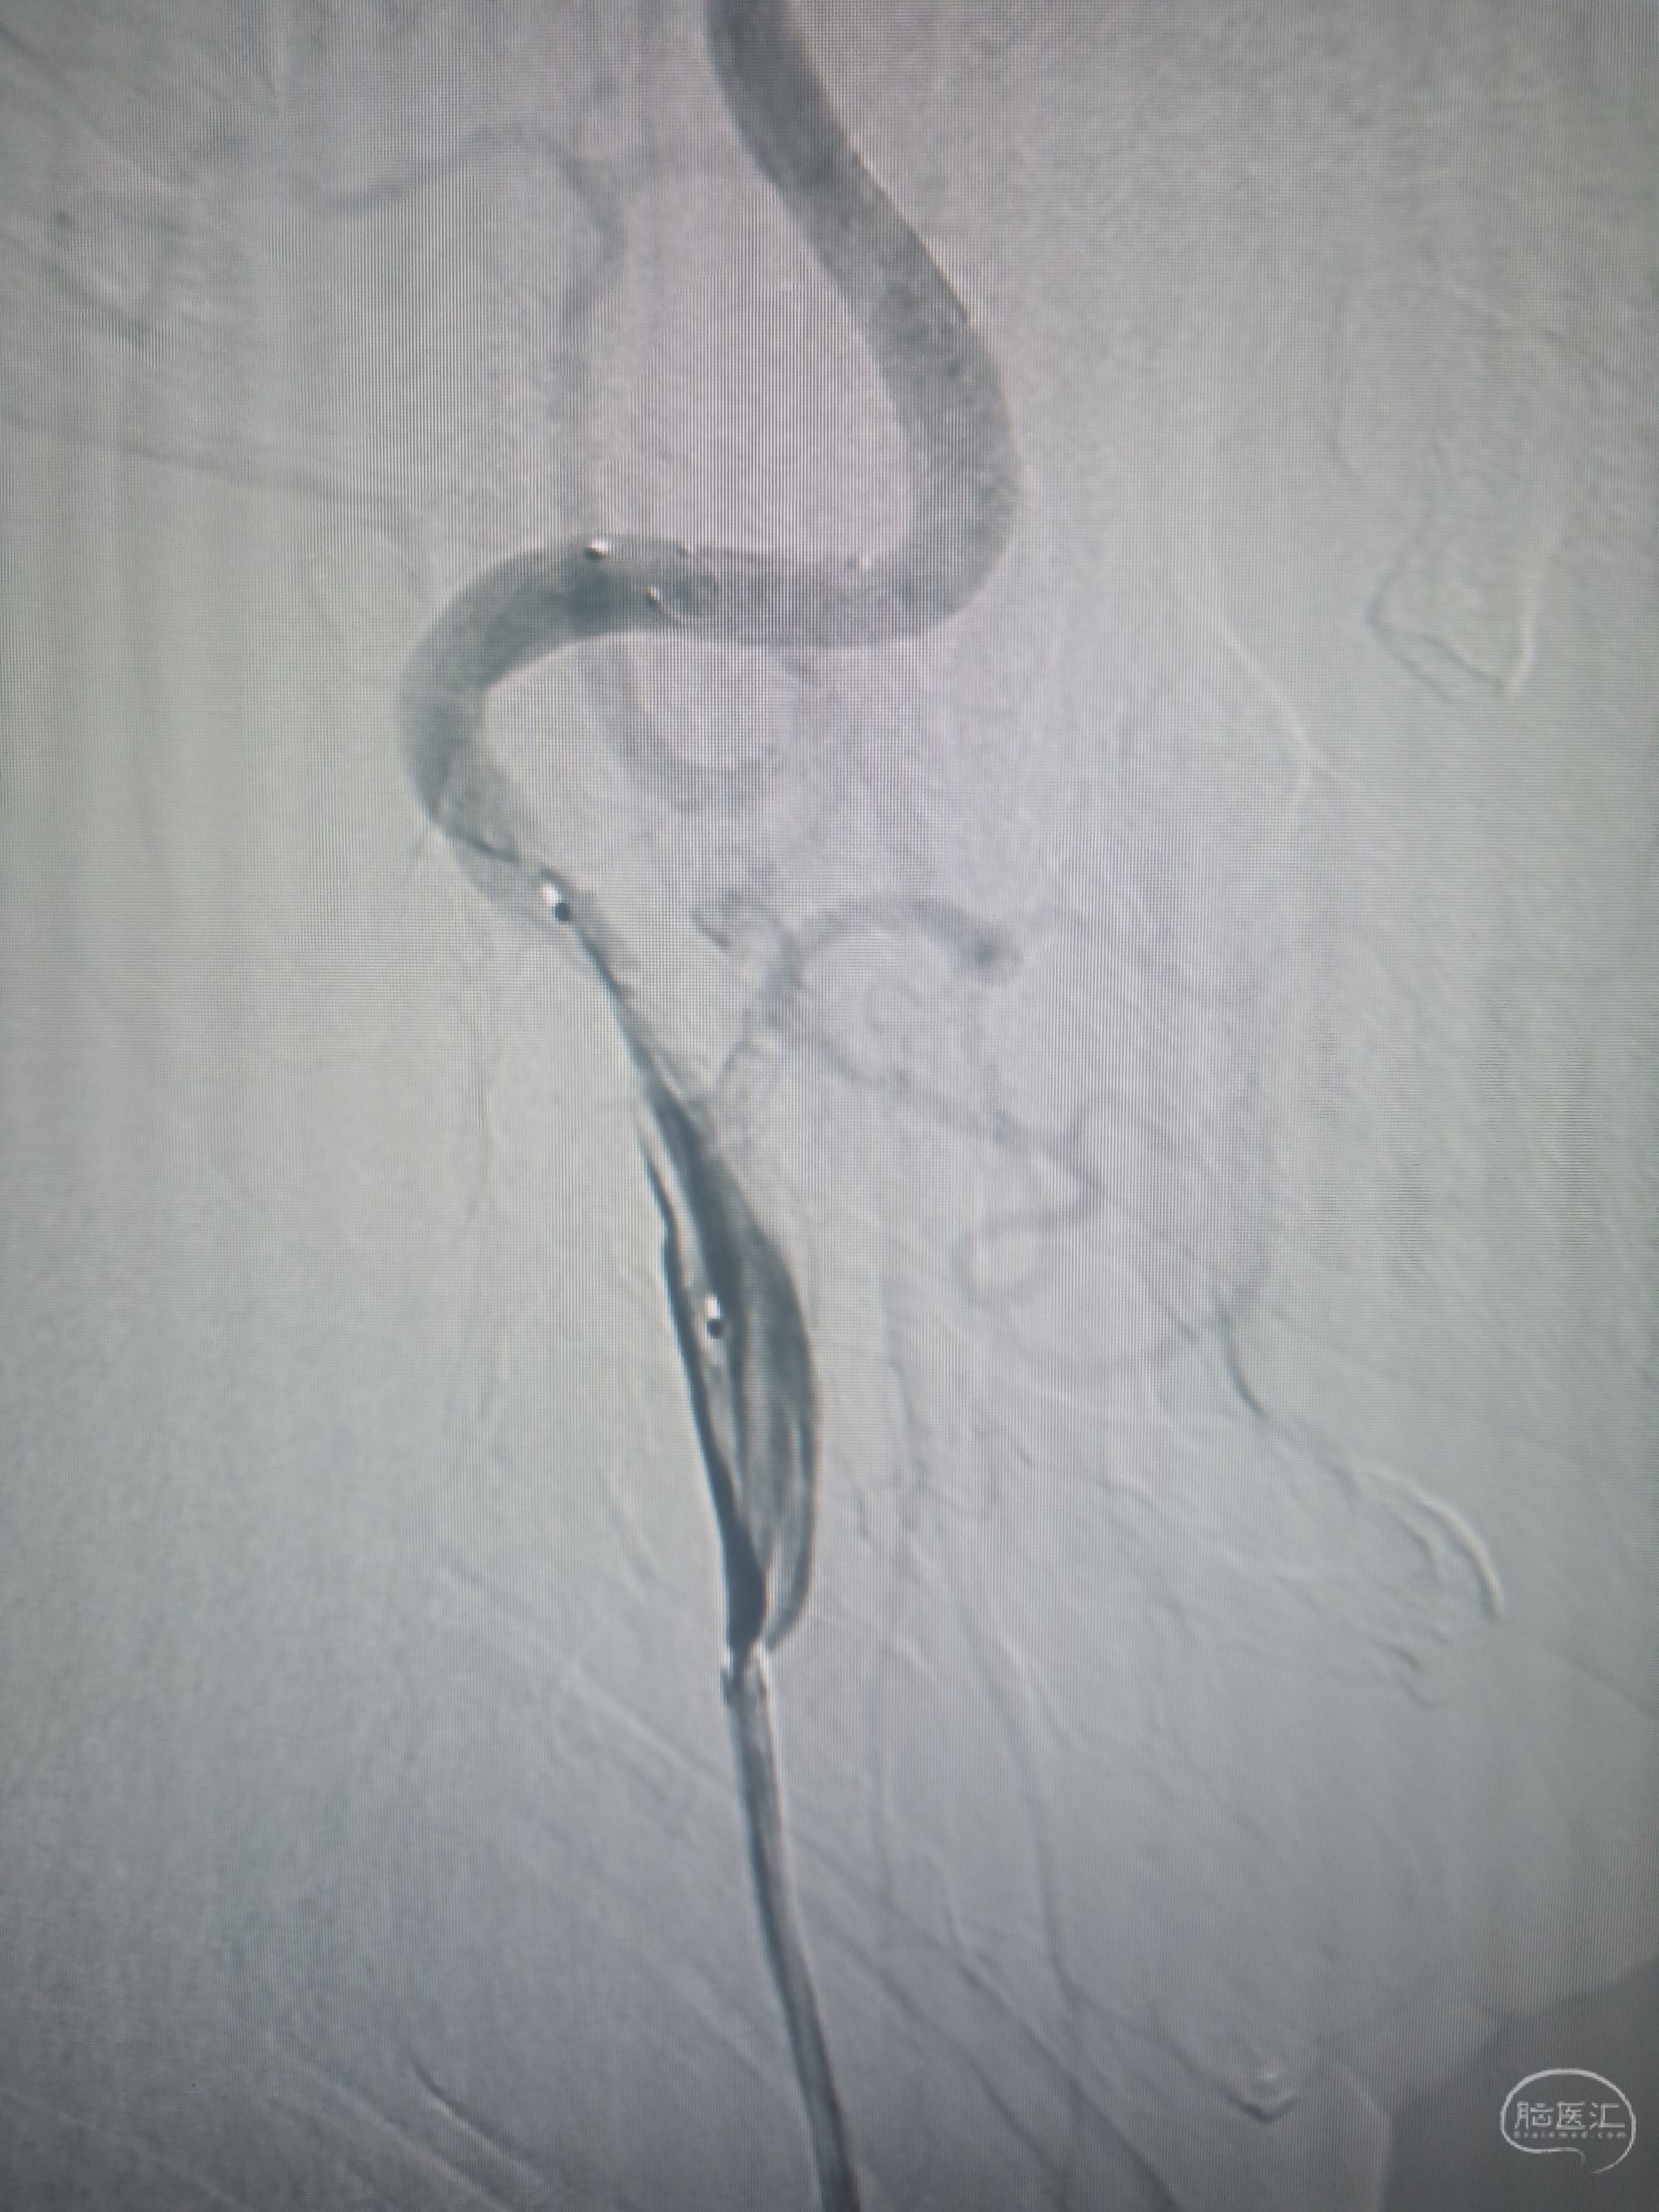

球囊铆定预扩张:用4mm球冠脉囊护张至命名压,泄压释放球囊。

球囊扩张示意图